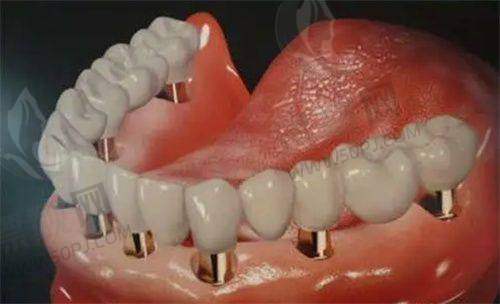

1)数字化种植牙技术:采用德国卡瓦(Kavo)设备,3D影像辅助下进行数字引导种植,听起来就高大上。